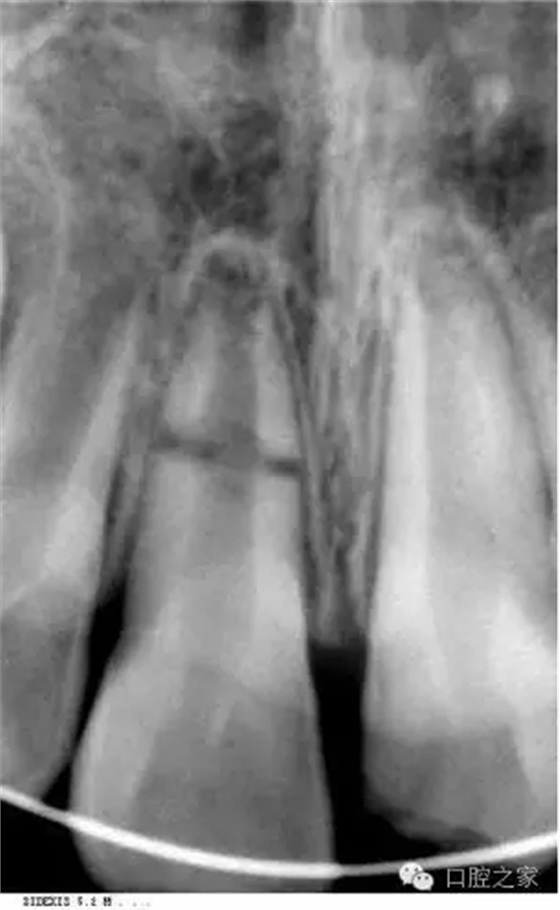

3.X線檢查: 牙折、骨折、牙周組織、鄰牙、牙胚、

牙根形成及吸收等)